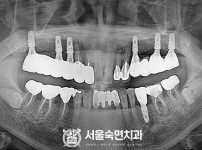

임플란트-전후사진2